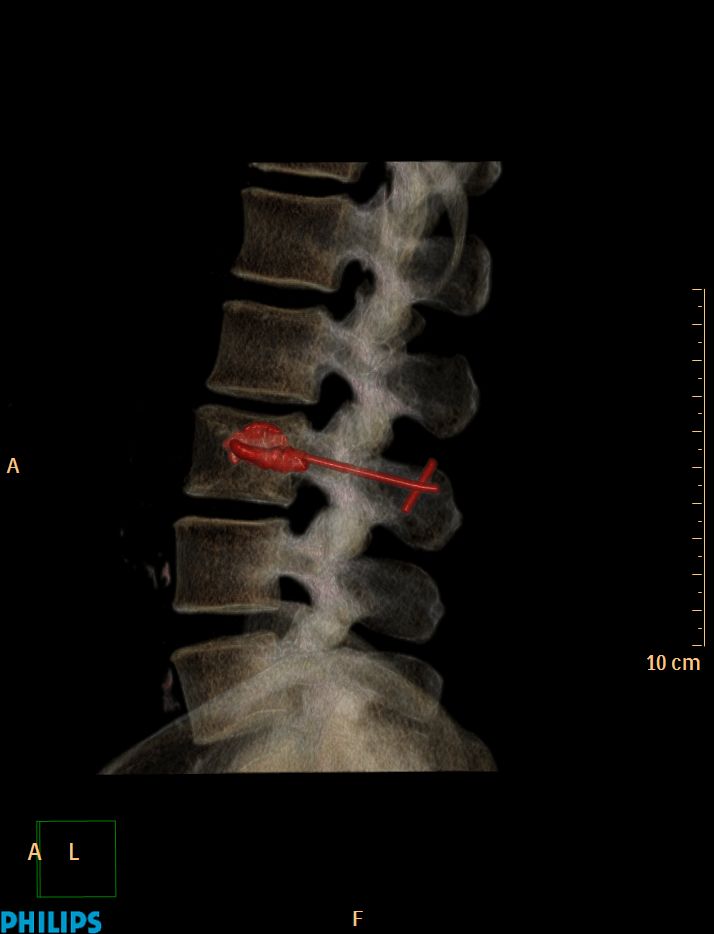

La vertébroplastie C'est ça d'attendre trop avant de retirer le trocard !!!